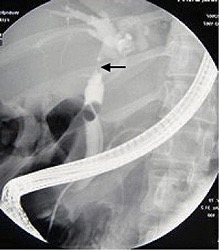

ERCP (Endoscopic retrograde cholangiopancreatography) refers to an endoscopic procedure. A flexible endoscope is passed down the gullet into the stomach and then into the intestine, and contrast medium (a dye that shows up on x-rays) is injected into the common bile duct. This shows up the level and extent of the blockage. A plastic or soft metal tube (called a stent) can then be pushed up through the blockage, to allow the bile to flow again. Bile samples, biopsy samples and brushings from the blockage can be sent to the pathology laboratory, to be checked for the presence of cancer cells. PTC (percutaneous transhepatic cholangiography) is a different procedure but with a similar intent. It involves needle puncture of the skin over the liver, and then of the liver substance. A fine tube is passed into the bile duct, under ultrasound guidance, and a stent can then be pushed across the blockage (but from above, in this instance). Again, bile samples, biopsies and brushings can be taken. The choice between PTC or ERCP is usually determined by local expertise, availability, and failure of one or the other technique, usually ERCP. PTC is preferable for higher strictures and often a combination of both procedures is required. These invasive techniques carry the risk of procedural complications including bleeding, biliary leakage, pancreatitis, cholangitis and duodenal perforation.

Picture taken at ERCP showing a cancerous obstruction high up in the common bile ductLaparoscopy (inspection of the abdominal cavity with a camera inserted through a keyhole incision) can sometimes detect small tumours and liver secondaries missed on other scans, though it is less accurate for blood vessel or lymph node involvement. The combination of laparoscopy with laparoscopic ultrasound may prevent an unnecessary attempt at surgery in some patients.